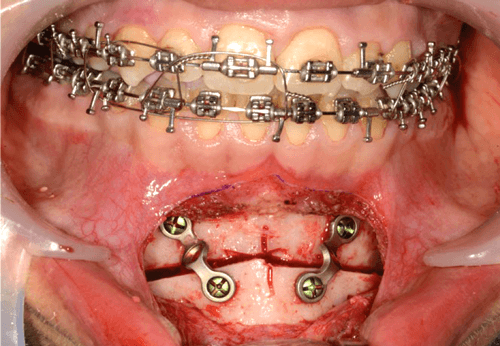

We use a reciprocating saw to perform the osteotomy cut in an inverted ‘v’ shaped fashion (Figure 3).

Figure 3.

Following down fracture of the distal segment, it is fully mobile and can be advanced into the pre-planned final position, ensuring good bone to bone contact between segments to optimise healing. The senior author fixes the osteotomised chin with two pre-bent 2.0 mandibular titanium plates (Figure 4).

Figure 4.